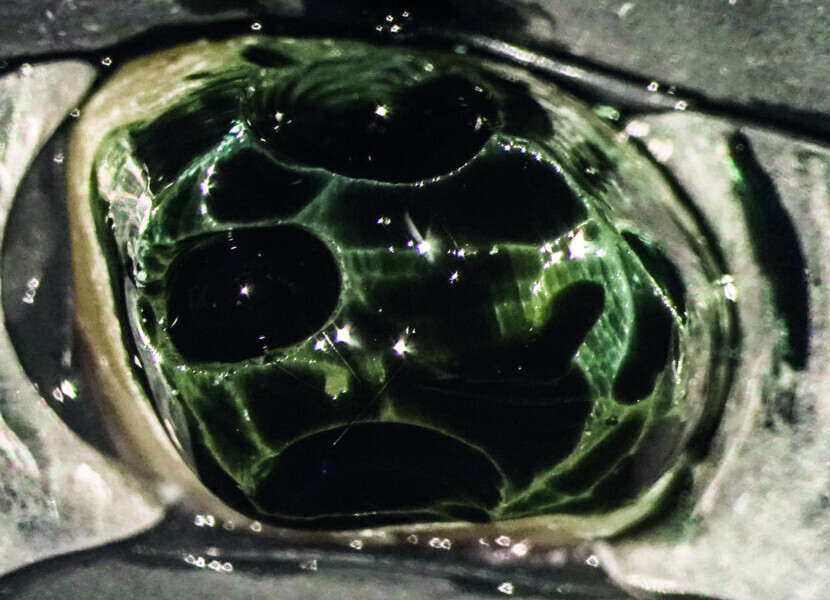

Minimally invasive root canal shaping—A new protocol